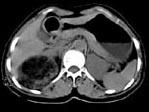

问题 女,53岁,右侧轻度腰背酸痛,行CT检查,如图所示,可能的诊断为 ( )

选项 A、右腹膜后脂肪瘤 B、右肾血管平滑肌脂肪瘤 C、右肾上腺腺瘤 D、右肾上腺嗜铬细胞瘤 E、右肾上腺髓样脂肪瘤

答案 E